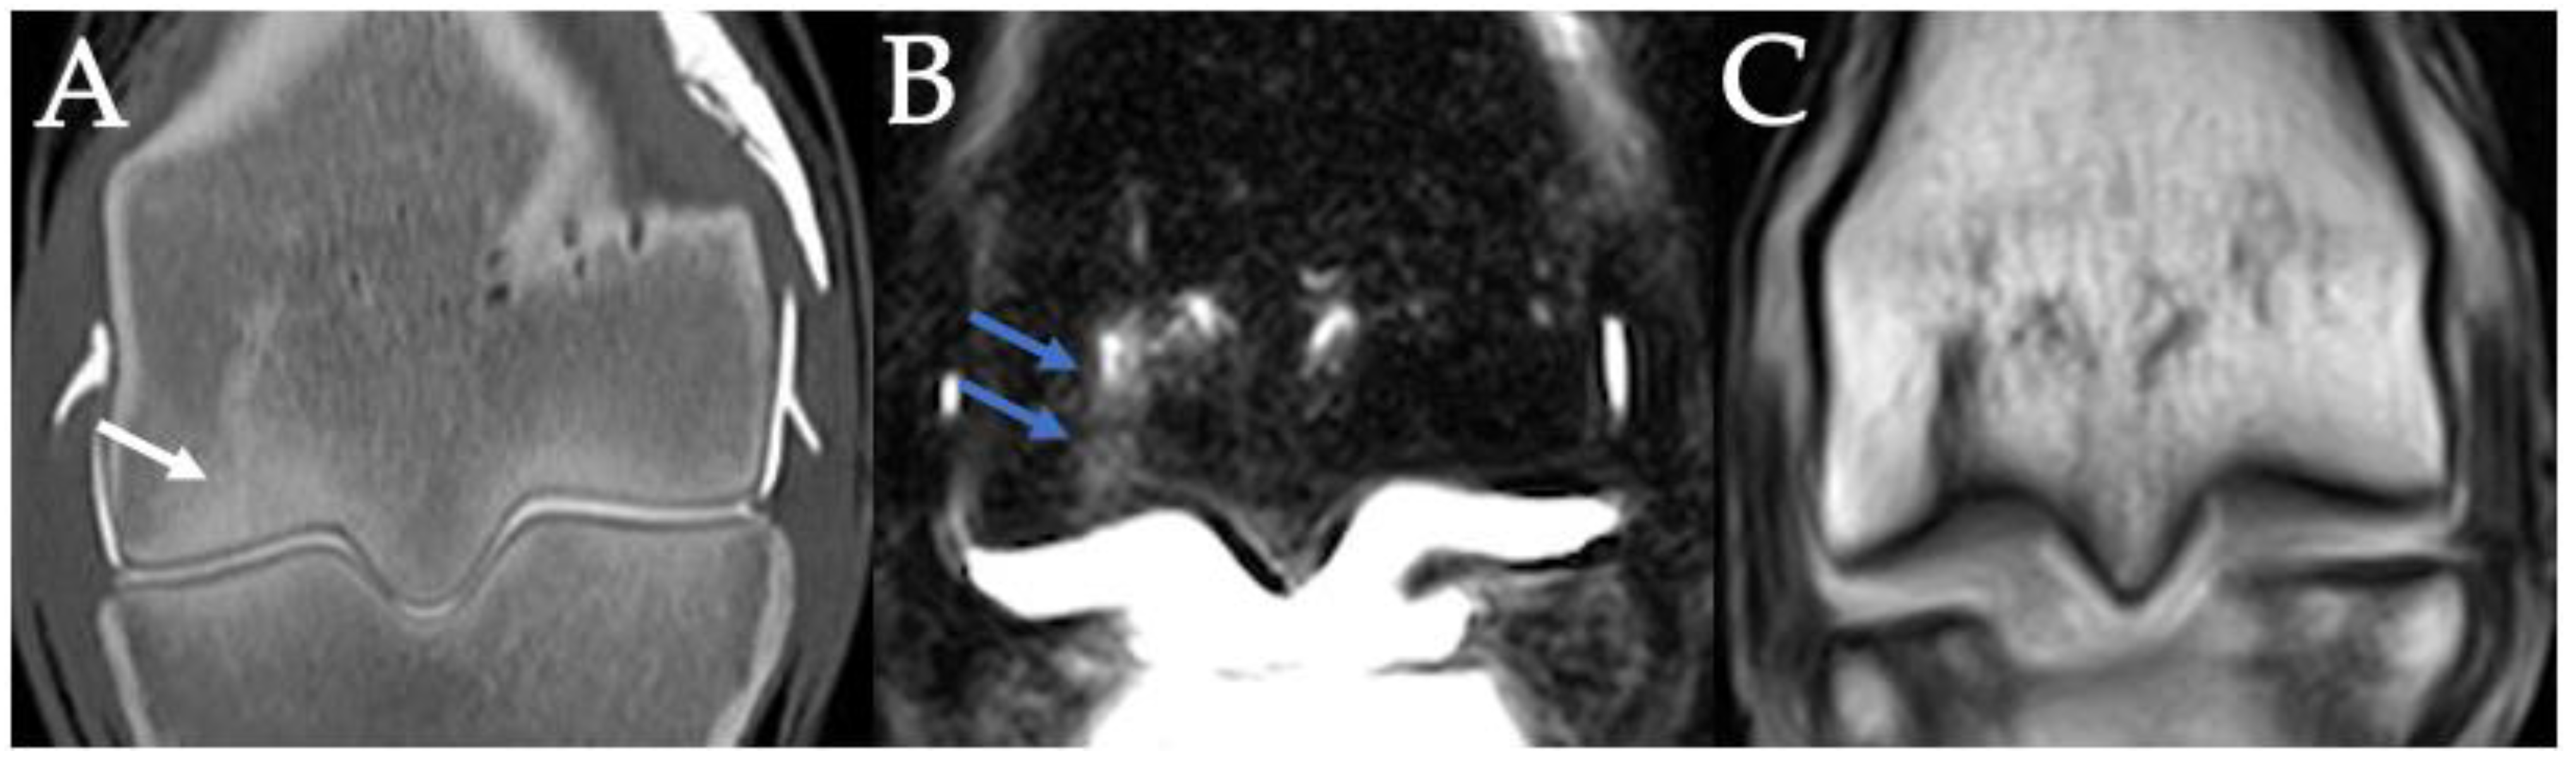

3.5. PSG Cartilage Defects

3.6. PSG STIR Hyperintensity